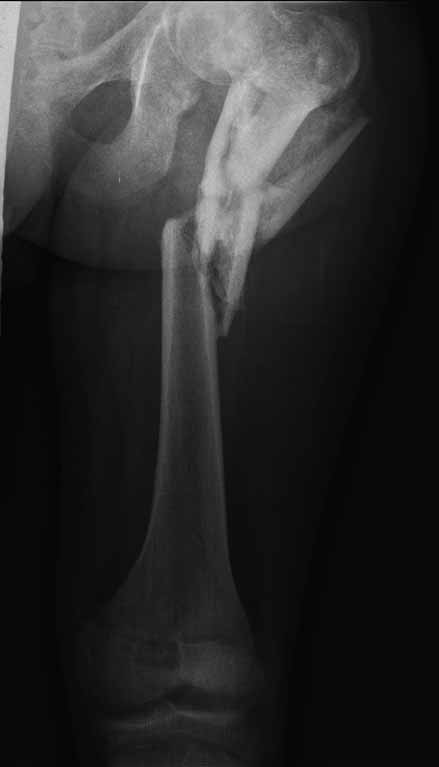

На лечении находится пациент с тяжелой сочетанной травмой. На сегодняшний день встал вопрос о тактике лечения переломов бедер( по месту жительства бедрами не занимались).

Пациенту 22 года. Травма в июле 2010г, лечился в районной больнице. К нам попал в апреле 2011г. Тяжелая сочетанная травма (29.07.2010): тупая травма живота с повреждением внутренних органов. Закрытая травма грудной клетки с переломом ребер. Пневмоторакс справа. Тяжёлая позвоночно-спинномозговая травма. Закрытый осложнённый переломо-вывих С5 позвонка. Верхний парапарез, нижняя параплегия, нарушение функции тазовых органов по типу недержания. Цекостома. Пролежень левой ягодичной области. Неправильно консолидированные переломы верхних третей обеих бедер. Застарелый вывих левого бедра. Осложнение: Поддиафрагамльный абсесс слева, забрюшинного пространства. Свищ желудка и ободочной кишки. Синегнойный сепсис. Двухстороняя пневмония. Но это уже анамнез. Пациент был неоднократно оперирован на органах брюшной полости и осложнениями с ними связанными.

В ягодичной области слева глубокий пролежень размером 2х2см, дном является вывихнутая головка бедра. Неврологически в нижних конечностях динамика положительная, появились движения в правой стопе, чувствительность в стопах. По переломам бедер: подвижности в местах переломов нет, снимки высылаю.

Уважаемые коллеги, помогите определиться с оптимальной тактикой в лечении перелома бедер. Степень оснащенности у нас достаточная (аппараты, штифты, пластины, ЭОП).

Планирую начать с правого бедра, ЧКО таза (передняя рама) с фиксацией бедра. О/клазия места перелома правого бедра и устранение грубых смещений в аппарате. окончательно можно оставить и в аппарате. Далее аппаратное устранение вывиха левого бедра.